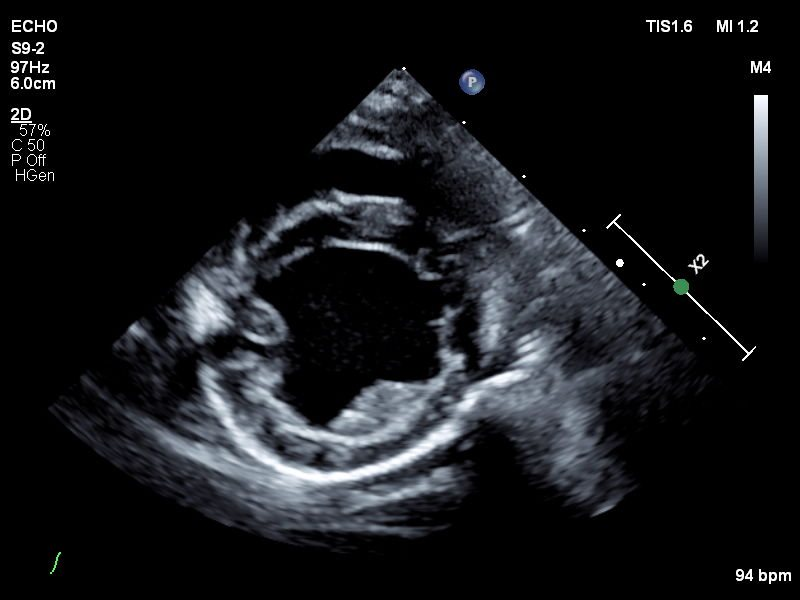

Echocardiograms

Veterinary echocardiography is a type of ultrasound imaging that focuses on the heart.

Echocardiography assesses the structure and function of an animal's heart. This non-invasive

procedure employs ultrasound technology to produce detailed, real-time images of the

heart's chambers, valves, and blood flow. Echocardiography is essential for diagnosing

and monitoring heart conditions such as heart murmurs, cardiomyopathy, and valve disorders.